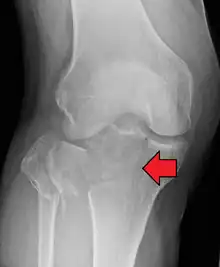

| A severe tibial plateau fracture with an associated fibular head fracture | |

A tibial plateau fracture seen on X-ray